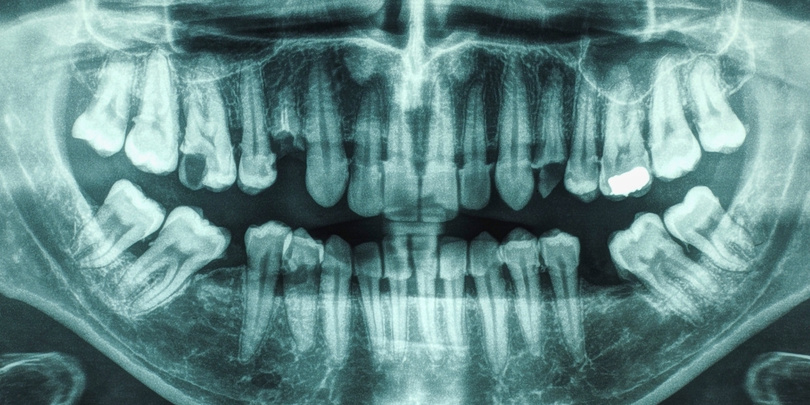

ღრძილების დაავადება და კარიესი ინსულტის გაზრდილ რისკთან დააკავშირეს

საკმაოდ გახშირდა კვლევები, რომლებიც პირის ღრუს პრობლემებს ისეთ მდგომარეობებთან აკავშირებს, როგორიც, მაგალითად, დემენცია და დიაბეტია. ახლა მეცნიერებმა გამოავლინეს, რომ ამგვარი ასოციაციაა ინსულტთანაცაა, როცა ღრძილების დაავადება და კარიესი შეინიშნება. მათი კომბინაცია, როგორც რიკს-ფაქტორი, ერთად აქამდე იშვიათად განხილულა — უფრო მეტად ყურადღება მათ ცალ-ცალკე ექცეოდა.

"აღმოვაჩინეთ, რომ ერთდროულად ღრძილების დაავადებისა და კარიესის მქონე ადამიანები ინსულტის ორჯერ დიდი რისკის წინაშე იყვნენ, ვიდრე ისინი, ვისი ორალური ჯანმრთელობაც დამაკმაყოფილებელი იყო. ეს მაშინაც კი, როცა გულ-სისხლძარღვთა რისკ-ფაქტორები კონტროლდებოდა", — აცხადებენ მეცნიერები.

მათ საშუალოდ 63 წლის ასაკის 5 986 ინდივიდი შეისწავლეს, რომელთა მდგომარეობასაც 21 წელი აკვირდებოდნენ. მონაწილეთაგან მანამდე არცერთს ჰქონია გადატანილი იშემიური ინსულტი, გულის კორონალური დაავადება ან მხოლოდ კარიესი, ღრძილების პრობლემის გარეშე.

ისინი სამ ჯგუფად დაჰყვეს: კარგი ორალური ჯანმრთელობის, ღრძილების დაავადებისა და მასთან ერთად კარიესის მქონედ. დადგინდა, რომ ინსულტი პირველთა მხოლოდ 4.1%-ში დაფიქსირდა, მეორეში 6.9%-ში, მესამეში კი — 10%-ში.

შემდეგ მკვლევრებმა ისეთი ფაქტორები გაითვალისწინეს, როგორიც სხეულის მასის ინდექსი და მწეველობაა. ამის შედეგად საბოლოო გამოთვლებმა აჩვენა, რომ ღრძილების პრობლემის მქონენი ინსულტის 44%-ით მეტი რისკის წინაშე იყვნენ, ვიდრე ჯანმრთელები. თუკი მათ კარიესიც აღენიშნებოდათ, ეს მაჩვენებელი 86%-ზე ადიოდა.

რა იწვევს ასეთ ასოციაციას, ზუსტად დადგენილი არაა. შესაძლოა, მიზეზი ანთებითი პროცესი და პირის ღრუდან ორგანიზმში ბაქტერიების გავრცელება იყოს, რაც არტერიებს აზიანებს. დენტალური პრობლემების კომბინაციის 81%-ით თავიდან აცილება სტომატოლოგთან რეგულარული ვიზიტითაა შესაძლებელი, ღრძილების შემთხვევაში კი კვლევამ რისკის 29%-იანი შემცირება აჩვენა.